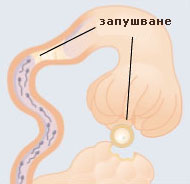

HSG Хистеросалпингографията (HSG) е рентегнова снимка използвана за установяване на запушвания на тръбите и маточни проблеми. Инжектира се контрастно вещество през шийката на матката и се прави рентгеновата снимка. Това изследване се прави обикновено след менструация и преди овулация.инжектирано контрастно вещество |

Адхезии (сраствания) (тъканни сраствания формирани от инфекция във фалопиевите тръби) могат да увредят и дори да запушват тръбите. Често хирургическата намеса е решение на проблема ако тръбите не са много увредени. Слузеста запушалка може да запуши фалопиевата тръба в близост до матката. Проблемът се решава чрез вмъкването на тънък катетър през маточната шийка в запушената тръба. Стерилизиране на тръбата има, когато те се намира в много тежко състояние. Може да бъде възстановена посредством микрохирургия, като се позволи на сперматозоидите да преминават през нея. |

Ако фалопиевите тръби са запушени, наранени, възможно е сперматозоидите да не могат да преминат през тях и да достигнат яйцеклетката. Често проблема се решава с хирургична намеса. |